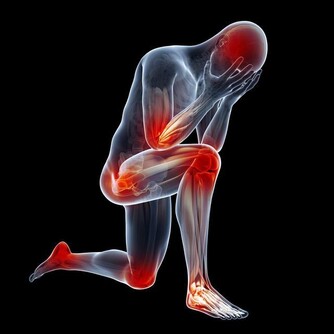

疲倦乏力

疲倦乏力程度自輕度疲倦感覺至嚴重乏力,與肝病的活動程度一致,產生乏力的主要原因有三:

1. 進食的熱量不足;碳水化合物、蛋白質、脂肪等的中間代謝障礙,致能量產生不足;

2. 肝臟損害或膽汁排泄不暢時,血中膽鹼酯酶減少,影響神經、肌肉的正常生理功能;

3. 乳酸轉化為肝醣原的過程發生障礙,肌肉活動後,乳酸蓄積過多。